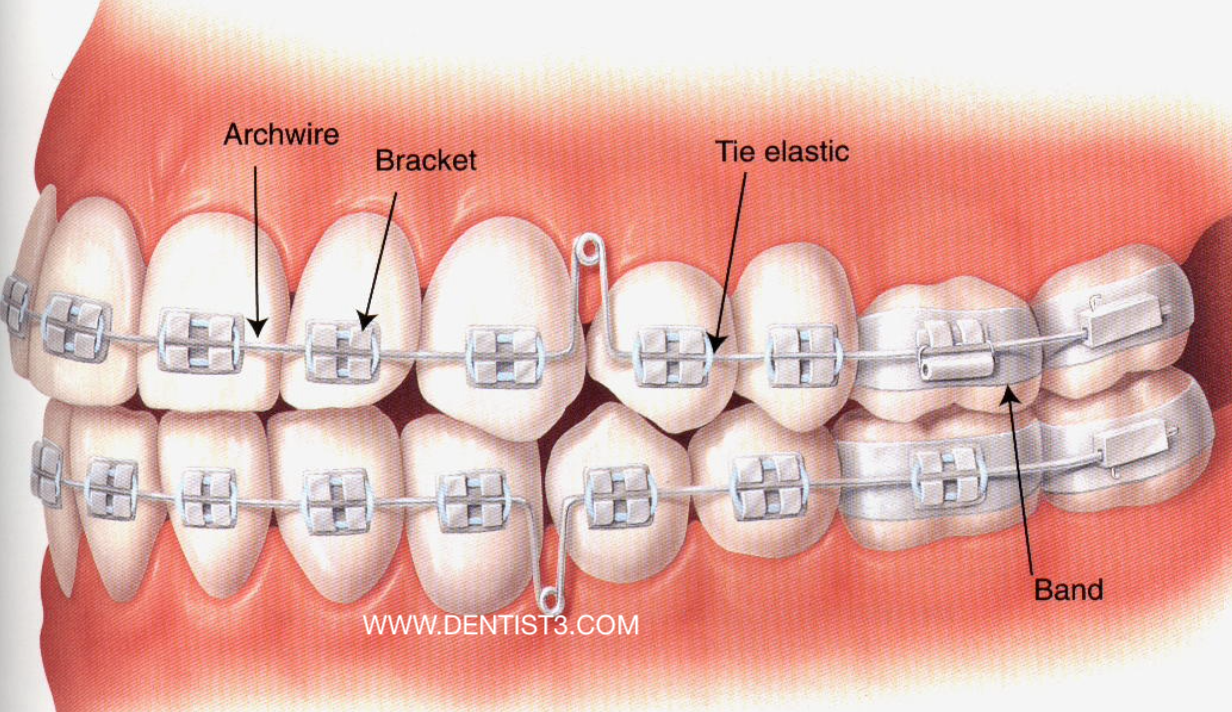

Understanding 10 Common Questions About Orthodontics Braces Malaysia Dental Clinics Dentists Klinik Gigi 牙医 In Malaysia

Self Ligating Braces How They Differ Benefits Cost